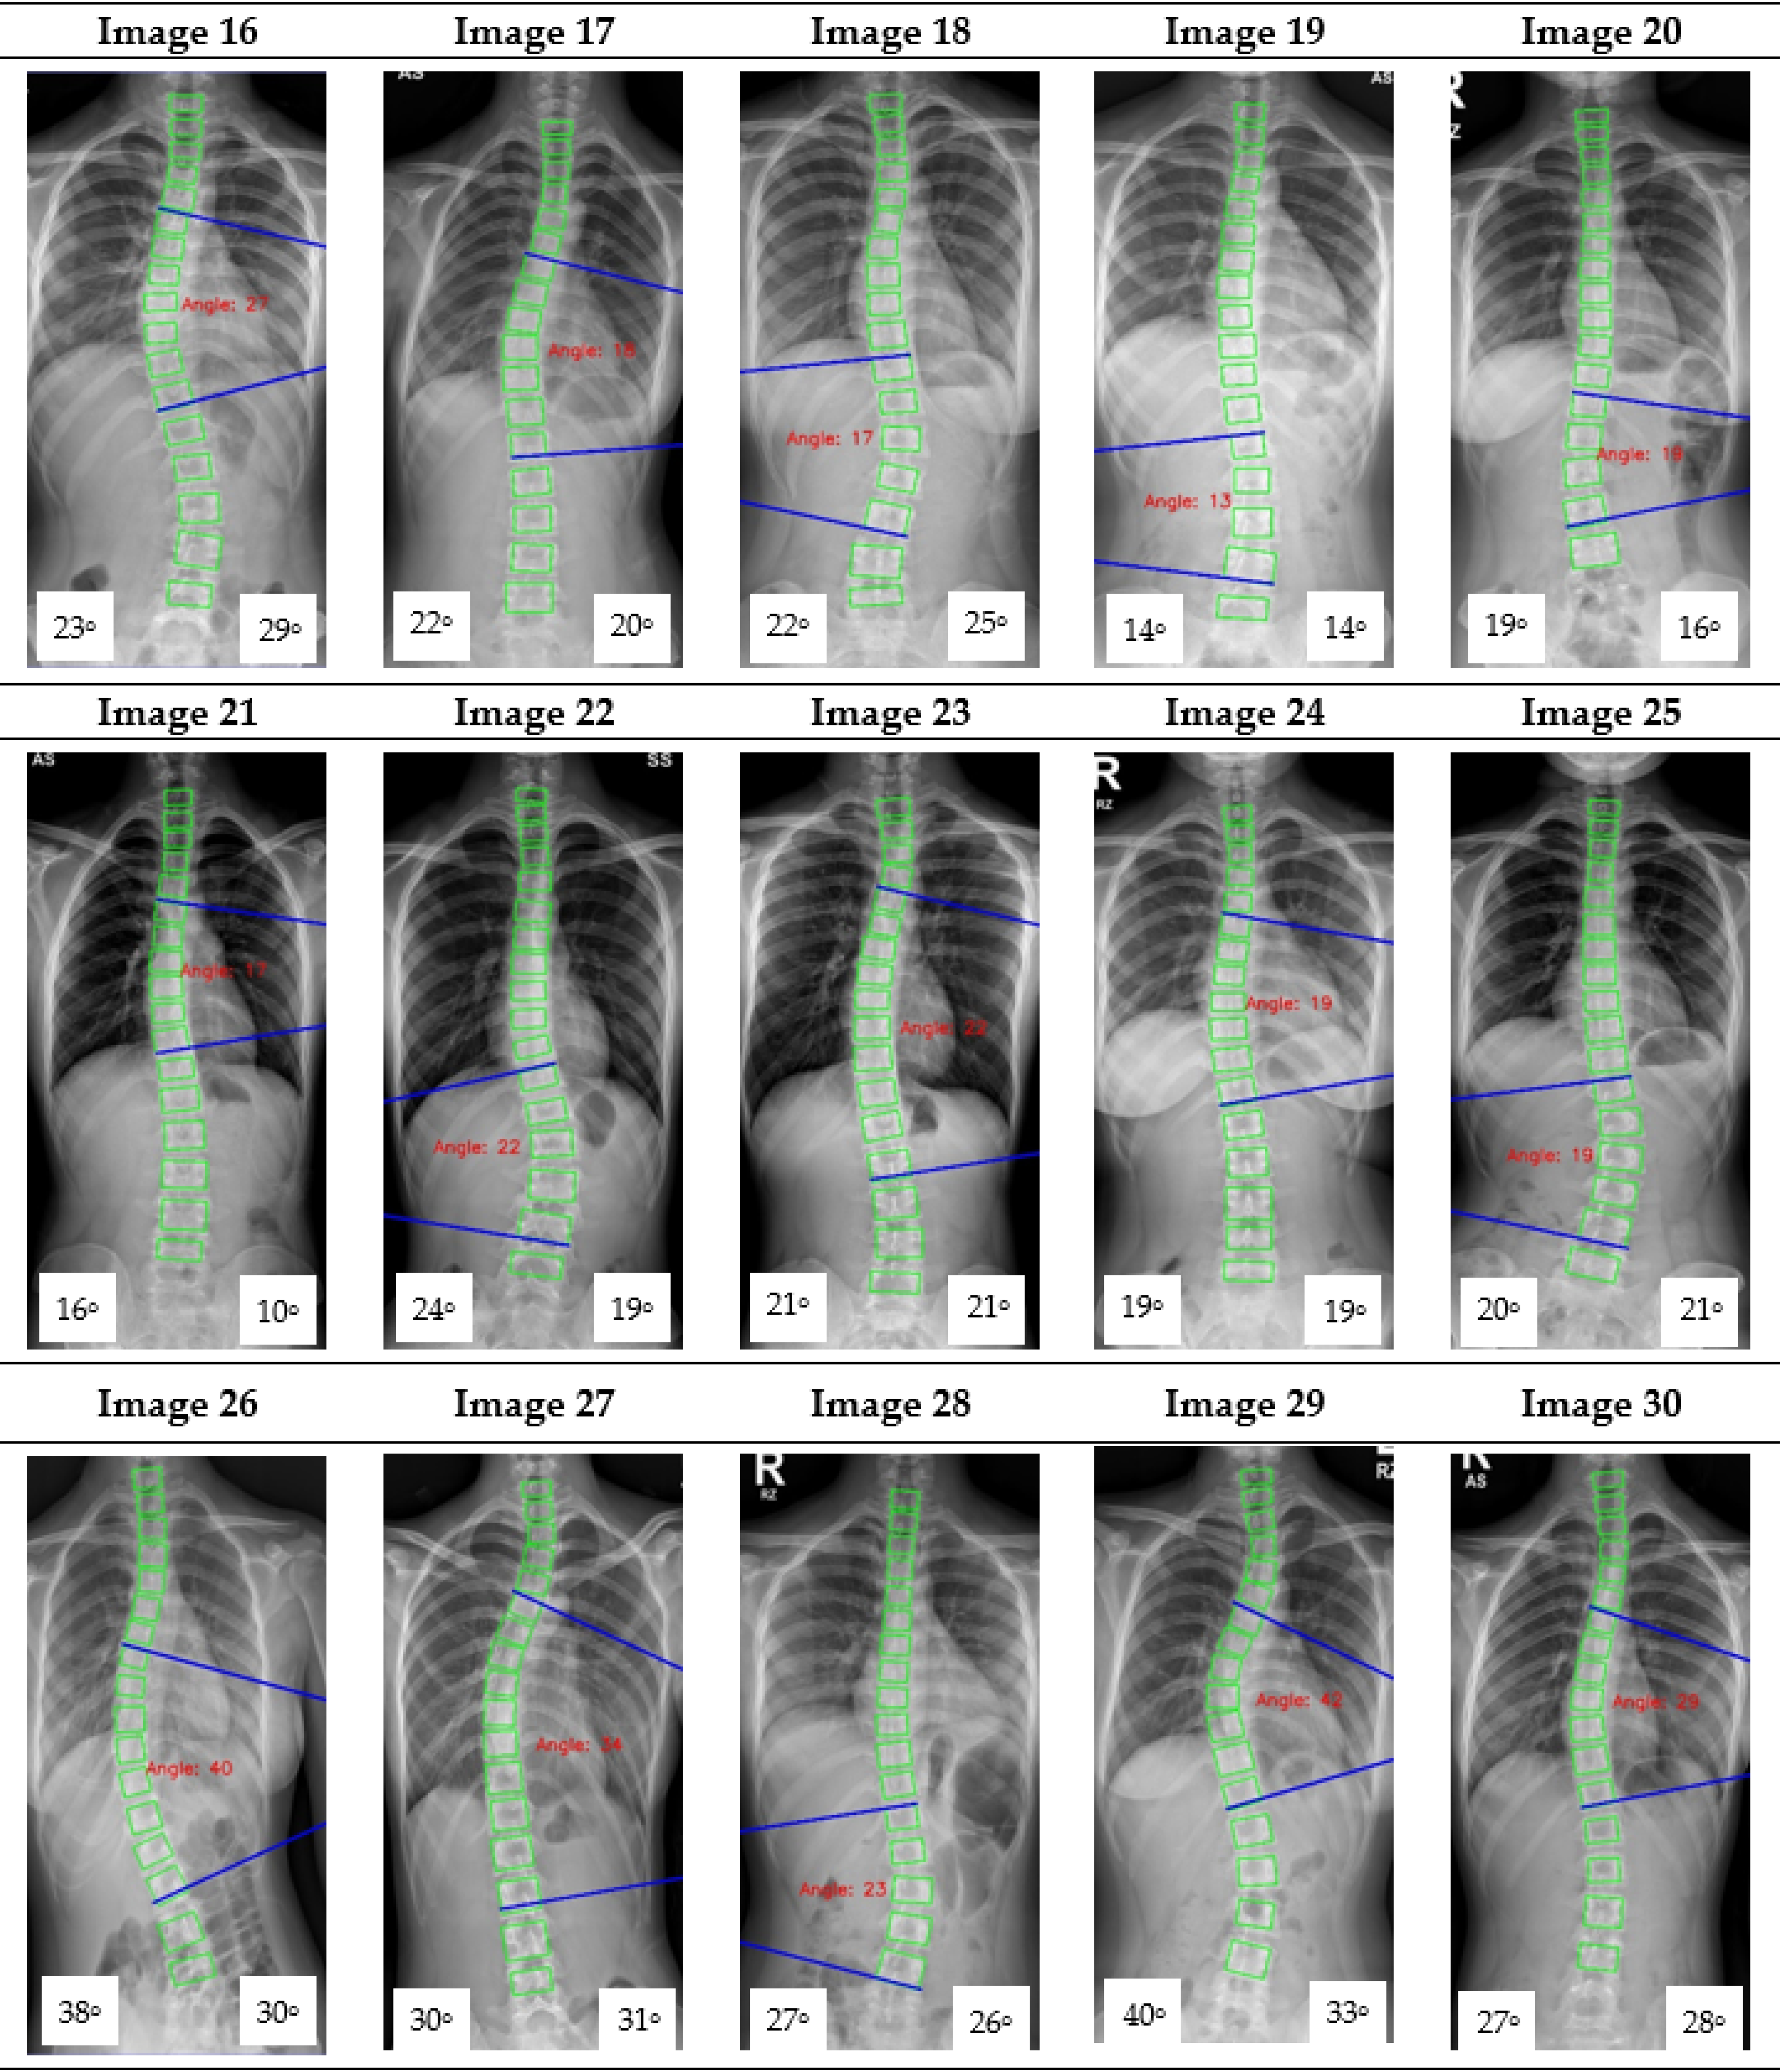

Appendix A. CNN Cobb Angle (CA) Measurement of X-ray Images

Figure A1.

The red font inside the X-ray image is a CNN CA measurement. Observer 1 and 2 evaluation is presented on the bottom left and right, respectively.